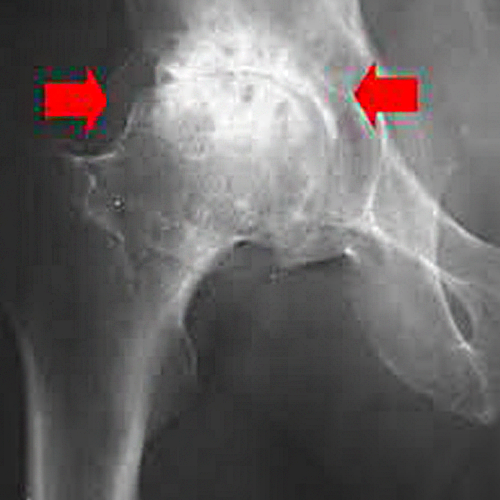

Некроз тазобедренного сустава: Фотографии и особенности лечения